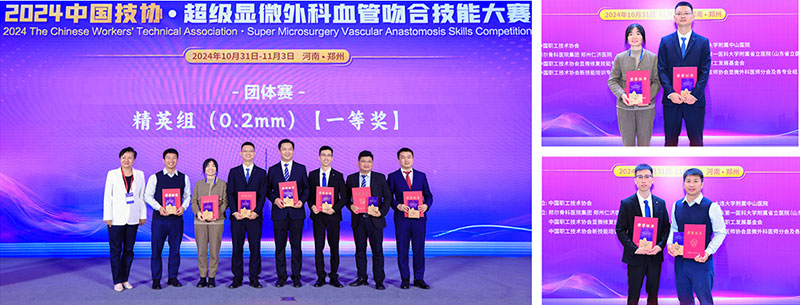

2024��11��3���й���Э�����������Ѫ���Ǻϼ��ܴ����������ݺ�ƽ�ǿ�ҽԺ�����ҽ���ŶӴ��ڶ�IJ�������Ͳ���ѡ������ӱ������ն��������һ�Ƚ������˾�Ӣ�����Ƚ������Ƚ���

���ݺ�ƽ�ǿ�ҽԺ������Ŷ��������С����Ժ���������������μ�����ҽ���Ĵ����£���ȫ�����̨ͬ������ƾ�衰�߾��⡱������Խ�����������ڶ�ǿ����������ӱ������ն������0.2mm�����������Ƚ�������0.2mm ��������Ӣ���صȽ���һ�Ƚ������Ƚ���һ����